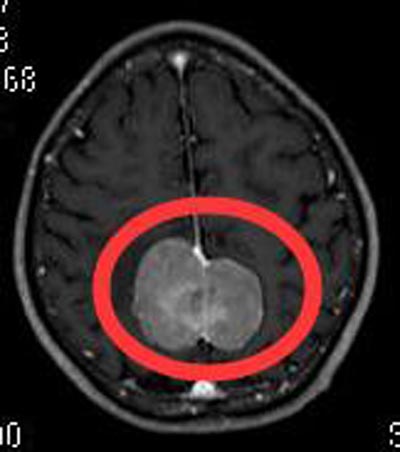

入住广东三九脑科医院综合神经外科,头颅MR检查提示:顶部镰旁两侧占位性病变,大小约47mm×41mm×40mm,考虑脑膜瘤可能性大。

家属要求手术治疗,由鲁明主任主刀,在全麻下行双侧顶部镰窦脑膜瘤切除术,显微镜下见灰白色肿瘤组织,质中,边界较清,与大脑镰粘连紧密,予显微镜下分块切除,保护下矢状窦,全切两侧肿瘤,手术过程顺利。术后刘爷爷四肢肌力正常,康复出院,术后病理结果提示:过渡型脑膜瘤 WHO I级。